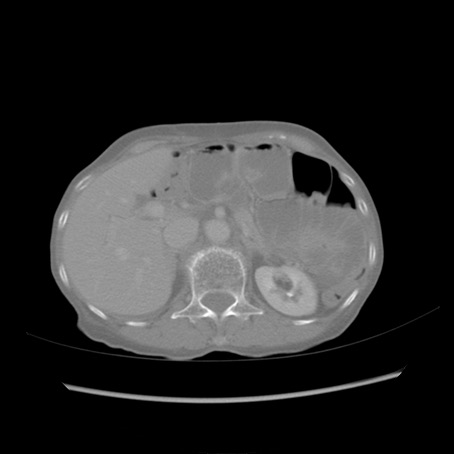

症例25(横断像)

【症例】80歳代女性

【主訴】胸のつかえ感

【現病歴】約9時間前に食後から胸のつかえた感じあり、嘔吐あり、来院。

【既往歴】胃癌(全摘)、胆摘、虫垂炎

【身体所見】心窩部に圧痛あり、反跳痛なし。

【データ】WBC 5700、CRP 0.05